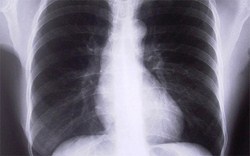

POChP czyli przewlekła obturacyjna choroba płuc to choroba w Polsce bardzo powszechna i często bagatelizowana. Szacuje się, że choruje na nią około dwóch milionów osób, a w ciągu roku umiera 15 tysięcy. Jak radzić sobie na co dzień z POChP będzie można dowiedzieć się podczas kursu przygotowanego przez CenterMed.

POChP to skrót nazwy „przewlekła obturacyjna choroba płuc”. Jest to choroba bardzo powszechna, a jej objawy często są niebezpiecznie długo bagatelizowane. W Polsce choruje na POChP około dwóch milionów osób, a co roku umiera w jej wyniku 15 tysięcy chorych.